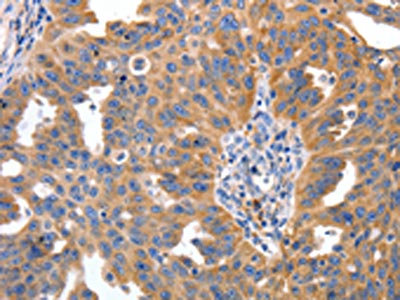

The image on the left is immunohistochemistry of paraffin-embedded Human ovarian cancer tissue using CSB-PA969280(IRS2 Antibody) at dilution 1/100, on the right is treated with synthetic peptide. (Original magnification: ×200)